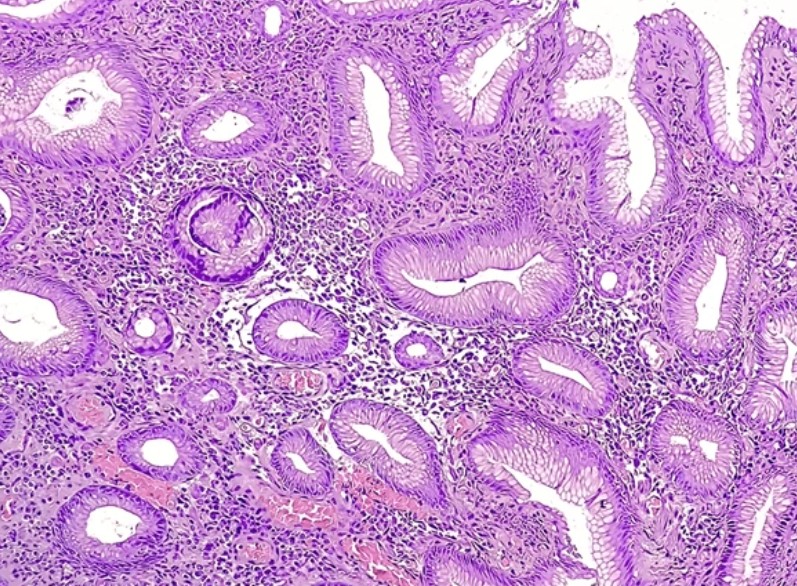

장기 감염에 의해 위 점막이 점차 손상되면 위축성 위염 → 장상피화생 → 위암으로 이어질 수 있습니다.

내시경을 통해 위 점막을 직접 관찰하며, 조직을 채취하여 헬리코박터 유무를 확인합니다.

내시경 중 위 점막을 일부 떼어내 균 배양 또는 분자진단(PCR)을 실시합니다.